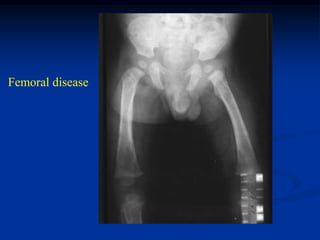

Case # 448

15 month male with LS skull

T-12 collapse

Femoral disease

Photomic